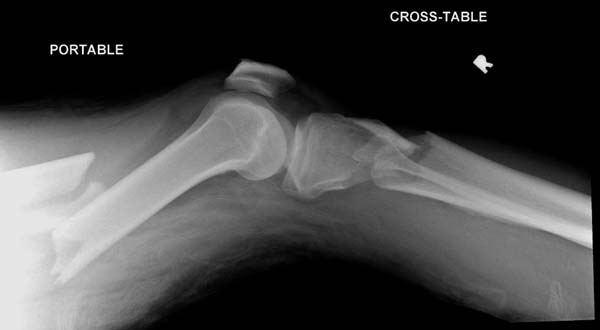

Здесь, кроме перелома верхней трети голени, имеется вовлечение сустава, и, чтобы не пропустить смещение суставной поверхности, надо делать КТ. Срезы КТ покажут о необходимости субхондральной фиксации, которая проводится 3.5 мм параллельными шурупами (Raft technique). Не имеет значения, как проводить: отдельно субхондрально или через верхний ряд пластины. Главная задача фиксации удержать суставную поверхность от коллапса в вальгус или варус.

Здесь случай, так называемого floating knee перелома выше и ниже коленного сустава.